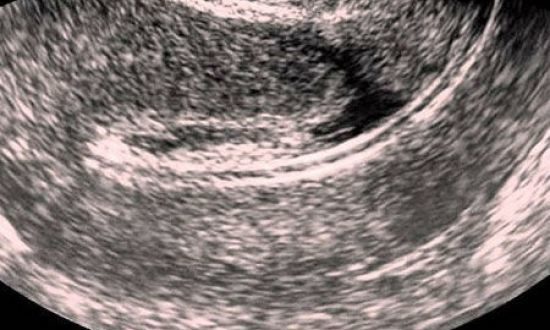

УЗИ после овуляции

Узи на овуляцию Процедура, помогающая определить день овуляции, называется фолликулометрией. Ее назначают в том случае, если у женщины появляются проблемы с зачатием ребенка. Фолликулометрия позволяет понаблюдать за процессом…